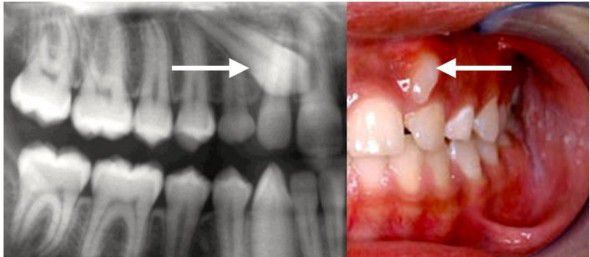

Impacted canine

Impacted canine tooth surgery is a dental procedure in which a canine tooth that is unable to properly erupt through the gum tissue and jawbone is surgically maneuvered into its functional position